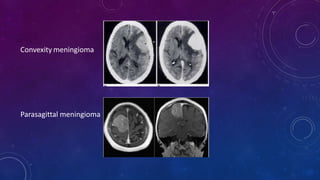

Convexity meningioma

Parasagittal meningioma

• The distributionof intracranial meningiomas is approximately as follows: convexity (35%), parasagittal (20%), sphenoid ridge (20%), intraventricular (5%), tuberculum sellae (3%), infratentorial (13%), and others (olfactory groove, cerebellopontine angle, etc) (4%).

LOCATION • The anatomiclocation of a meningioma influences its rate of recurrence. Tumors that are more difficult to remove totally, such as meningiomas of the sphenoid wing, recur more often. Meningiomas that invade a dural sinus, such as parasagittal meningiomas, have a high rate of recurrence. The recurrence rates of meningiomas differ from one series to another; the highest recurrence rates (>20%) are found in patients with sphenoid wing meningiomas, followed by those with parasagittal meningiomas (8% to 24%). The recurrence rate for convexity and suprasellar meningiomas is 5% to 10%.